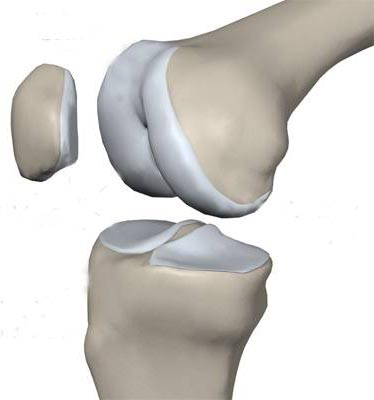

膝关节炎本质是关节软骨的慢性、进行性损伤,核心机制是“磨损” 与 “修复” 失衡:

1、关节软骨磨损:覆盖在骨头末端的弹性软骨像“缓冲垫”,因年龄增长、运动过量、反复劳损或炎症而变薄、碎裂、失去光滑。